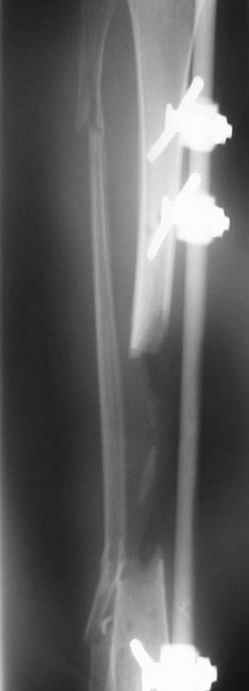

from case archives - also see Ilizarov split fibula

"fibula pro tibia" transfer for segmental tibia defects